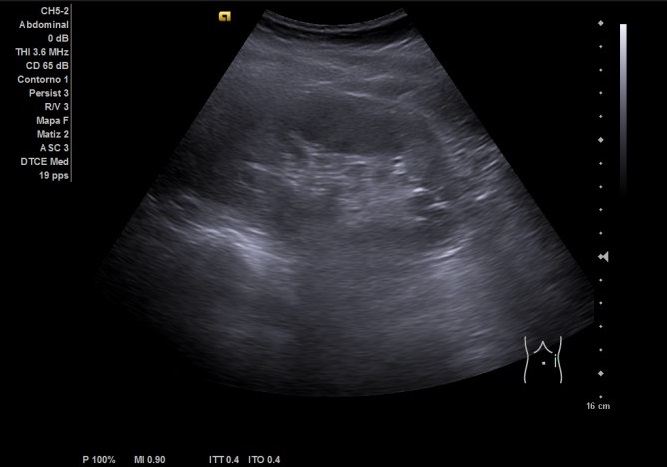

Riñón derecho ligeramente aumentado de tamaño con aparente hidronefrosis grado 1-2.

Riñón izquierdo tamaño y ecoestructura normal. Se visualiza vejiga con paredes homogéneas y ambos jets. Útero en anteversión, con mioma de 15,14 x 9,98 cm. Anejos normales.